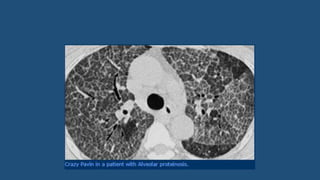

Crazy pavement phenomenon

• Crazy Paving is a combination of ground glass opacity with superimposed septal

thickening.

• It was first thought to be specific for alveolar proteinosis, but later was also seen

in other diseases.

• Crazy Paving can also be seen in:

• Sarcoidosis

• NSIP

• Organizing pneumonia (COP/BOOP)

• Infection (PCP, viral, Mycoplasma, bacterial)

• Neoplasm (Bronchoalveolar carcinoma (BAC)

• Pulmonary hemorrhage

• Edema (heart failure, ARDS, AIP)